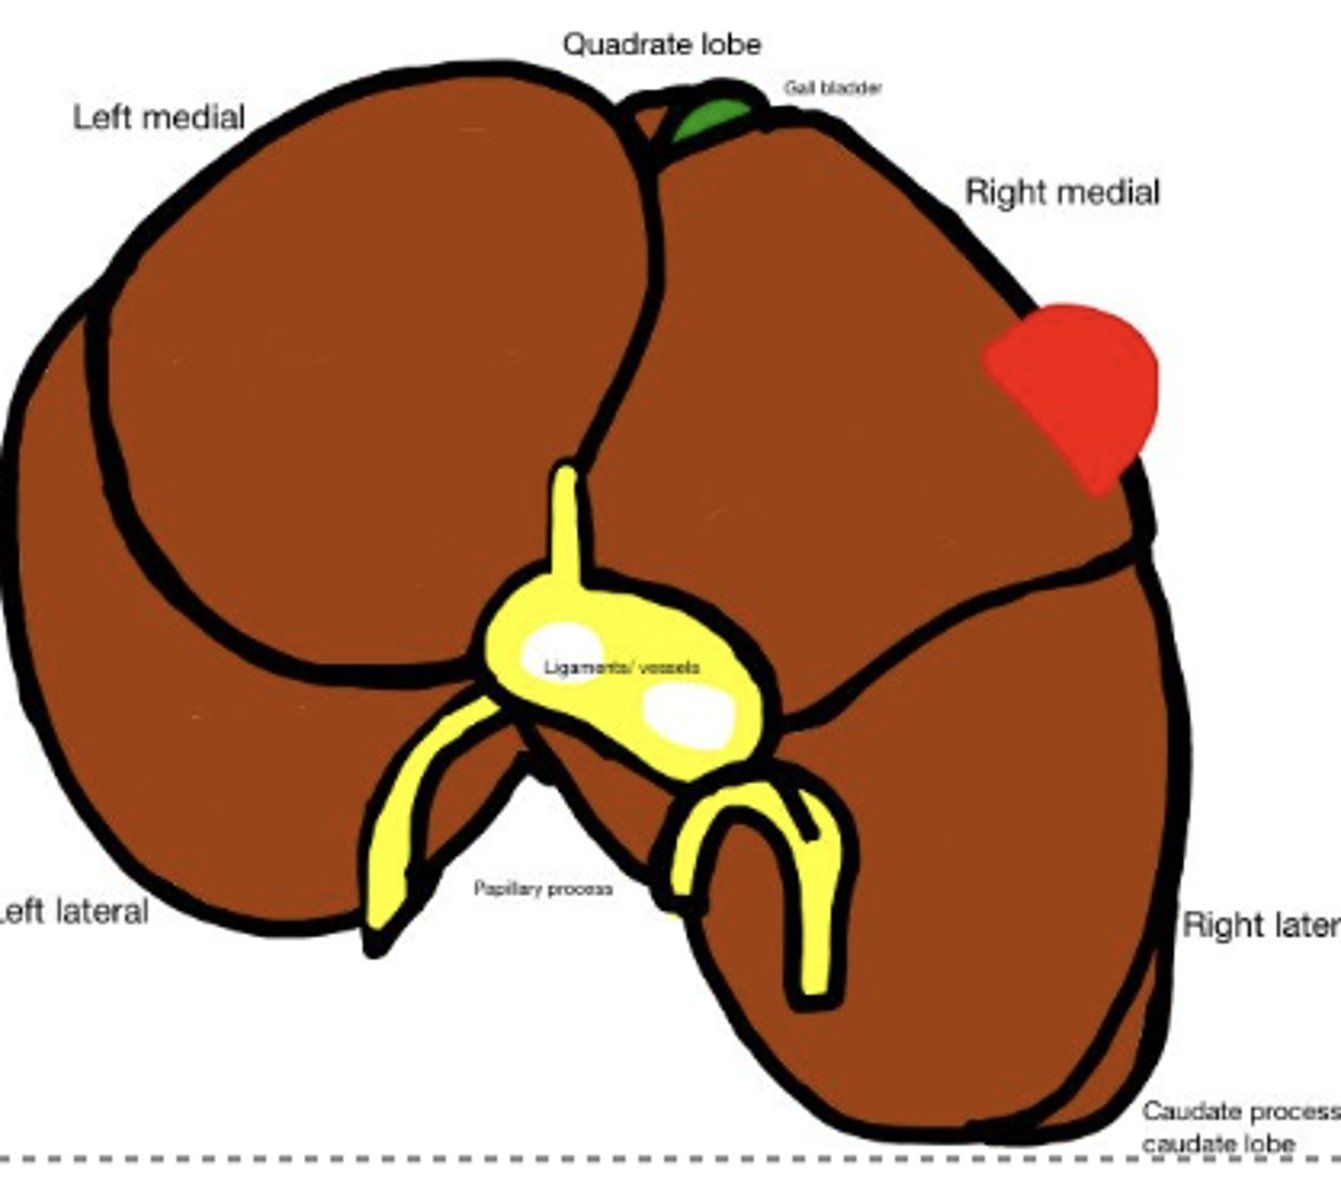

Mast cell tumor !!

-granulated

-red

What has caused this gross appearance of this liver?